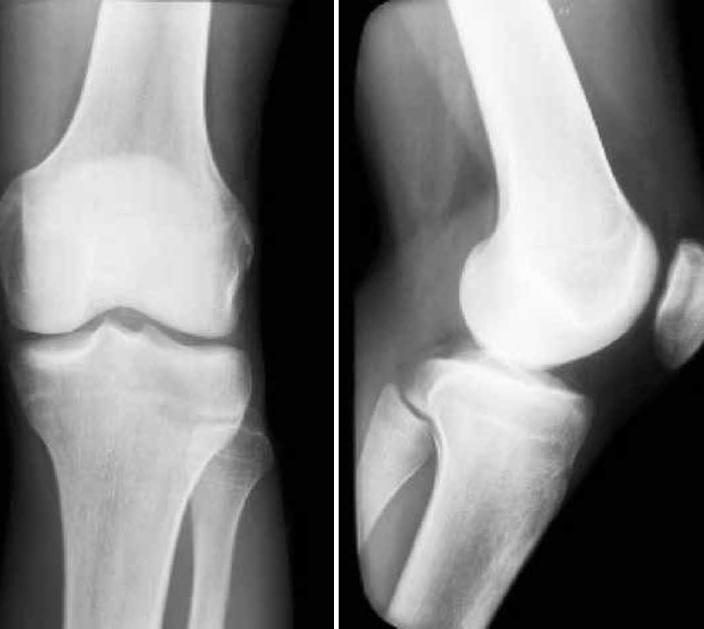

Dislocation of the femoral biceps tendon is rare and is described clinically in the literature as a lateral pain in the knee. It was initially reported as an anomalous insertion of the long head of the femoral biceps. Subsequently, it was found to be caused by abnormal mobility of the tendon over the prominence of the fibular head at certain angles of knee flexion. The objective of the present report was to describe and discuss a condition of lateral knee pain in a swimmer who started to present subluxation of the femoral biceps during sports practice, which incapacitated him from taking part in trials and competitions. The case is discussed in the light of the literature surveyed; the likelihood that the etiology for the trauma leading to this condition was repetition; and the surgical treatment instituted, which led to excellent results and the patient's return to his habitual sports practice.

股二头肌肌腱脱位较为罕见,在文献中临床描述为膝关节外侧疼痛。最初它被报道为股二头肌长头的异常附着。随后发现,它是由肌腱在膝关节屈曲一定角度时在腓骨头突出处的异常活动引起的。本报告的目的是描述和讨论一名游泳运动员膝关节外侧疼痛的情况,该运动员在体育训练中开始出现股二头肌半脱位,这使他无法参加选拔赛和比赛。结合所查阅的文献对该病例进行了讨论;导致这种情况的创伤病因很可能是重复性损伤;以及所采取的手术治疗,该治疗取得了优异的效果,患者恢复了其惯常的体育训练。